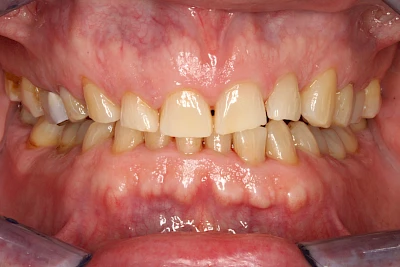

Über die Zeit können verschiedene Prozesse die Zahnhartsubstanzen aufzehren:

- Abnutzung durch Kauen (Abrasion) oder duch durch übermäßiges Knirschen bzw. Pressen (Attrition)

- Säurebedingte Auswaschung (Erosion)

- Knirschen bzw. Pressen und ungünstige Putztechnik (Druck): keilförmige Defekte

Die Zähne können dabei auf Reize (warm, kalt, süß, sauer) oder auch beim Zähneputzen empfindlich oder schmerzhaft sein. In allen diesen Fällen ist es sinnvoll, den Zahnarzt zu kontaktieren und das weitere Vorgehen abzustimmen.